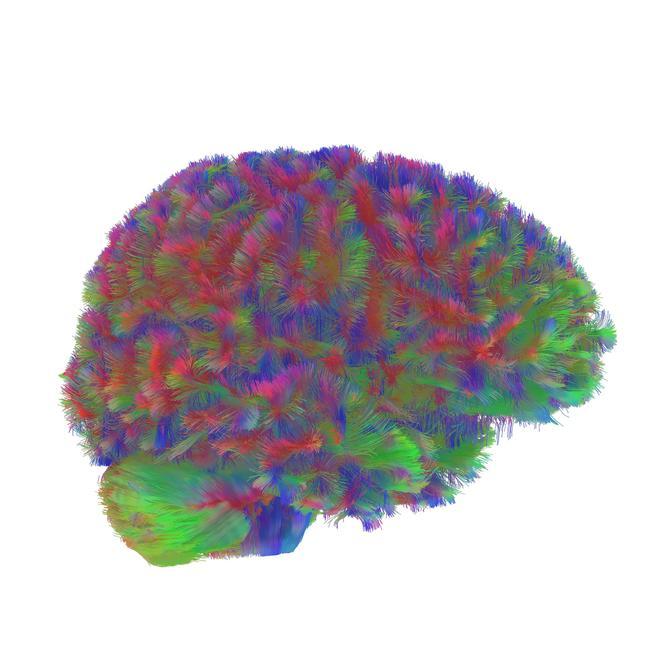

El cerebro humano pasa por cinco grandes etapas a lo largo de la vida. Se diferencian entre sí por cambios en la conectividad neuronal, y la transición tiene lugar a los 9, 32, 66 y 83 años, según ha identificado un estudio recogido este martes en la revista Nature Communications.